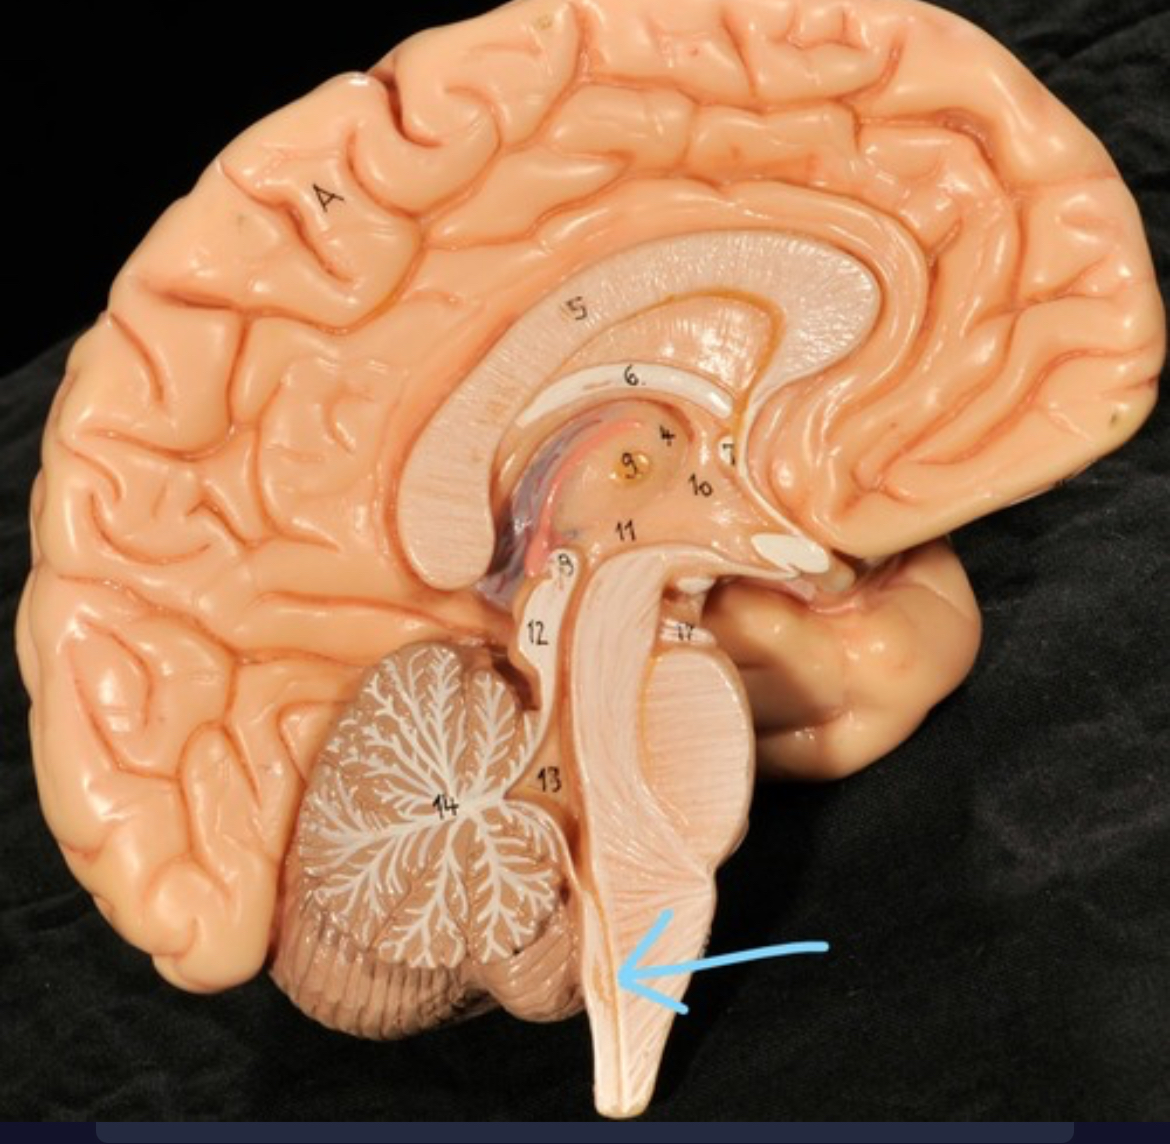

Cerebellum

Corpus callosum

Diencephalon

Thalamus

3rd ventricle

Hypothalamus

Epithalamus (pink line)

Brain stem

Pons

Medulla oblongata

Choroid plexus of 3rd ventricle

Cerebral aqueduct (midrain)

4th ventricle

central canal